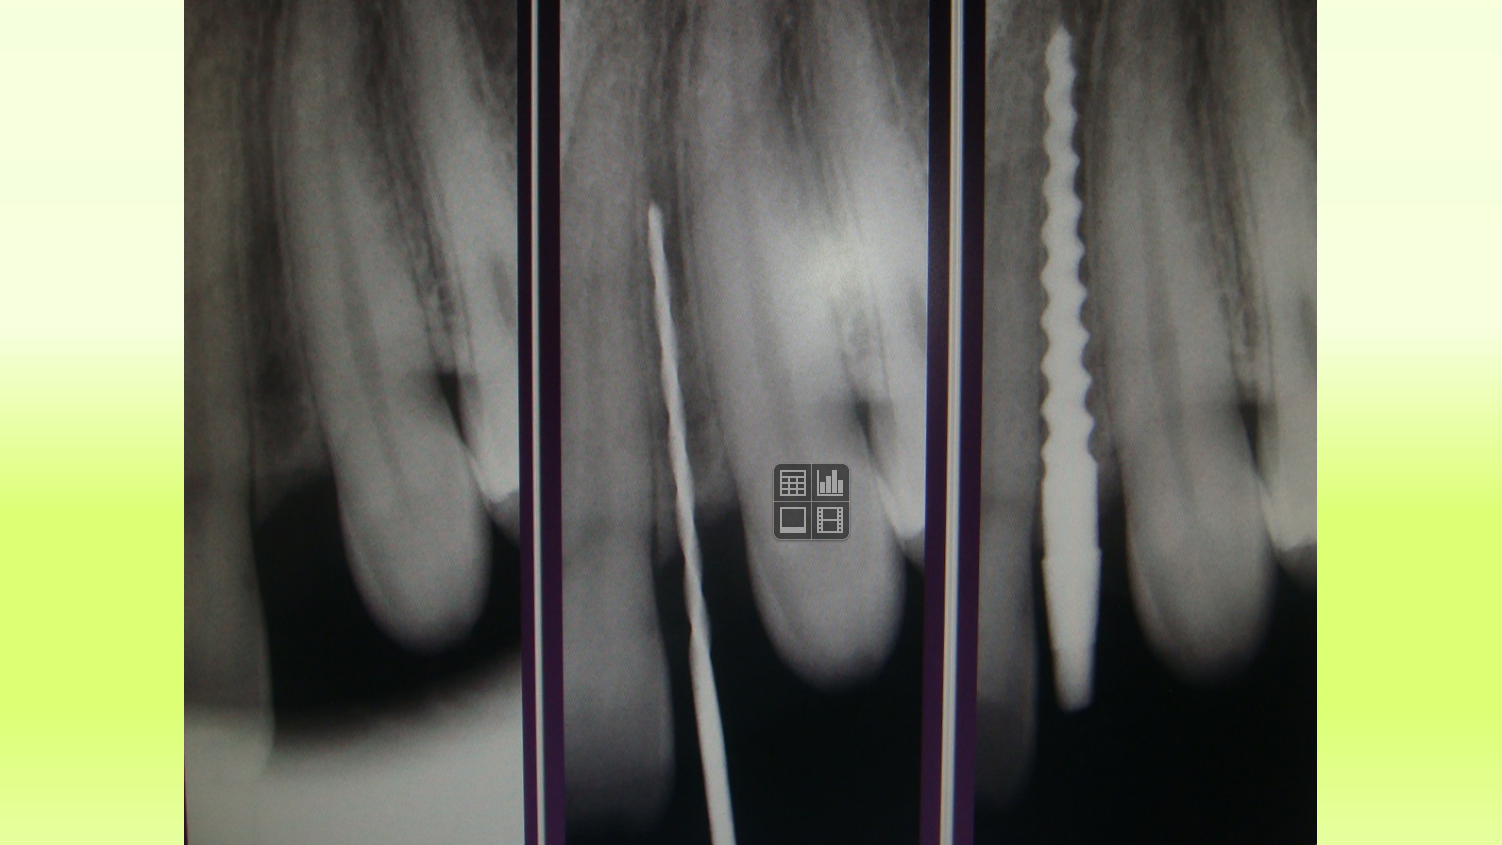

Case 12

“Vector” Implant placement in the area of 22 and 12 missing teeth is the only correct solution.